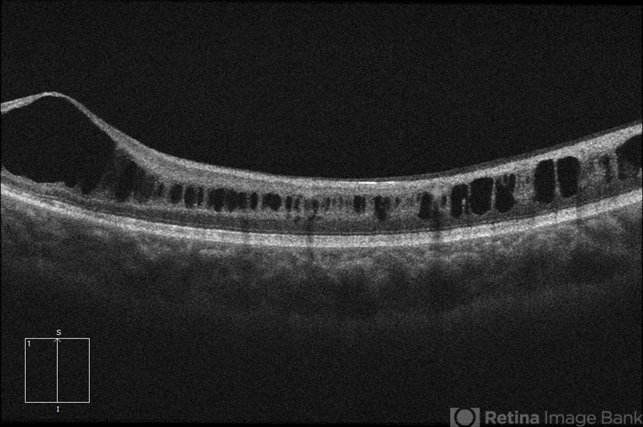

- retinoschisis, retinal hole

Optical coherence tomography system

Zeiss Cirrus 5000 - Description

- 21-year-old male with congenital retinoschisis with bilateral macular involvement and large inner retinal hole OD.